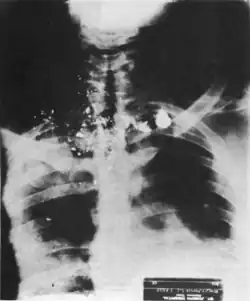

Relatório da Autópsia

Logo após King ser declarado morto, seu corpo foi transferido do Hospital São José para o Hospital John Gaston, onde o Dr. Jerry Francisco realizou uma autópsia por volta das 22h, publicada pela primeira vez em Condado de Shelby, Tennessee em 11 de abril de 1968.[1][37] Na época de sua morte, King foi descrito como medindo 1,77 m (5'9″, 176,5 cm) de altura, pesando cerca de 63,5 kg e tendo 39 anos de idade.[74]

O diagnóstico anatomopatológico realizado pelo Dr. Francisco indicou que:

Morte foi o resultado de um ferimento por arma de fogo no queixo e no pescoço com uma transecção total da cervical inferior e da medula espinhal torácica superior e de outras estruturas do pescoço. A direção do ferimento foi de frente para trás, de cima para baixo e da direita para a esquerda. O corte na medula espinhal [...] foi um ferimento que se mostrou fatal muito pouco tempo após sua ocorrência.[75]

— Dr. Jerry T. Francisco, relatório de autópsia de Martin Luther King Jr., página 1.

Foi ainda determinado que King foi atingido no lado direito do rosto, a cerca de 3,8 cm abaixo do "ângulo da boca". O projétil entrou pela mandíbula direita, adentrou a cavidade pleural direita, fraturou o osso da mandíbula e saiu pelo lado direito do queixo. O projétil então reentrou pela base do pescoço de King, continuando por sua fossa supraclavicular direita.[37][76] O projétil deixou um ferimento de 7,6 cm na bochecha direita de King, e feriu sua veia jugular externa, artéria vertebral e artéria subclávia, antes de se alojar próximo à parte de trás da escápula esquerda.[37][76]

Também foi observado uma cicatriz de 20,3 cm acima do peito direito de King e outra de 16,5 cm na parte superior do tórax. Contudo, essas cicatrizes foram atribuídas à tentativa de assassinato de 1958, não à bala disparada por Ray.[37][77] Após a remoção do projétil do corpo de King, determinou-se que não havia outras descobertas pertinentes. A causa oficial da morte foi listada como "colapso hemodinâmico por choque hemorrágico". Mesmo que King tivesse sobrevivido, determinou-se que os ferimentos causados à sua medula espinhal teriam o deixado quadriplégico.[37] King também apresentava um nível de álcool no sangue de 0,01% em amostras de seu sangue e urina.[74][77]

Foram recuperados 3 fragmentos de bala do corpo de King, encontrados em sua costas durante a autópsia, extraídos pelo Dr. Francisco.[74] Por fim, de acordo com Ben Branch, a autópsia de King revelou também que seu coração apresentava as características de um homem de 60 anos, em vez de um de 39, como King, fato que Branch atribuiu ao estresse decorrente dos 13 anos de envolvimento de King no movimento dos direitos civis.[78]